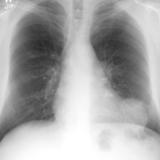

Case 1 PA

Peric calcification

Date: 03/17/2004

Views: 2585